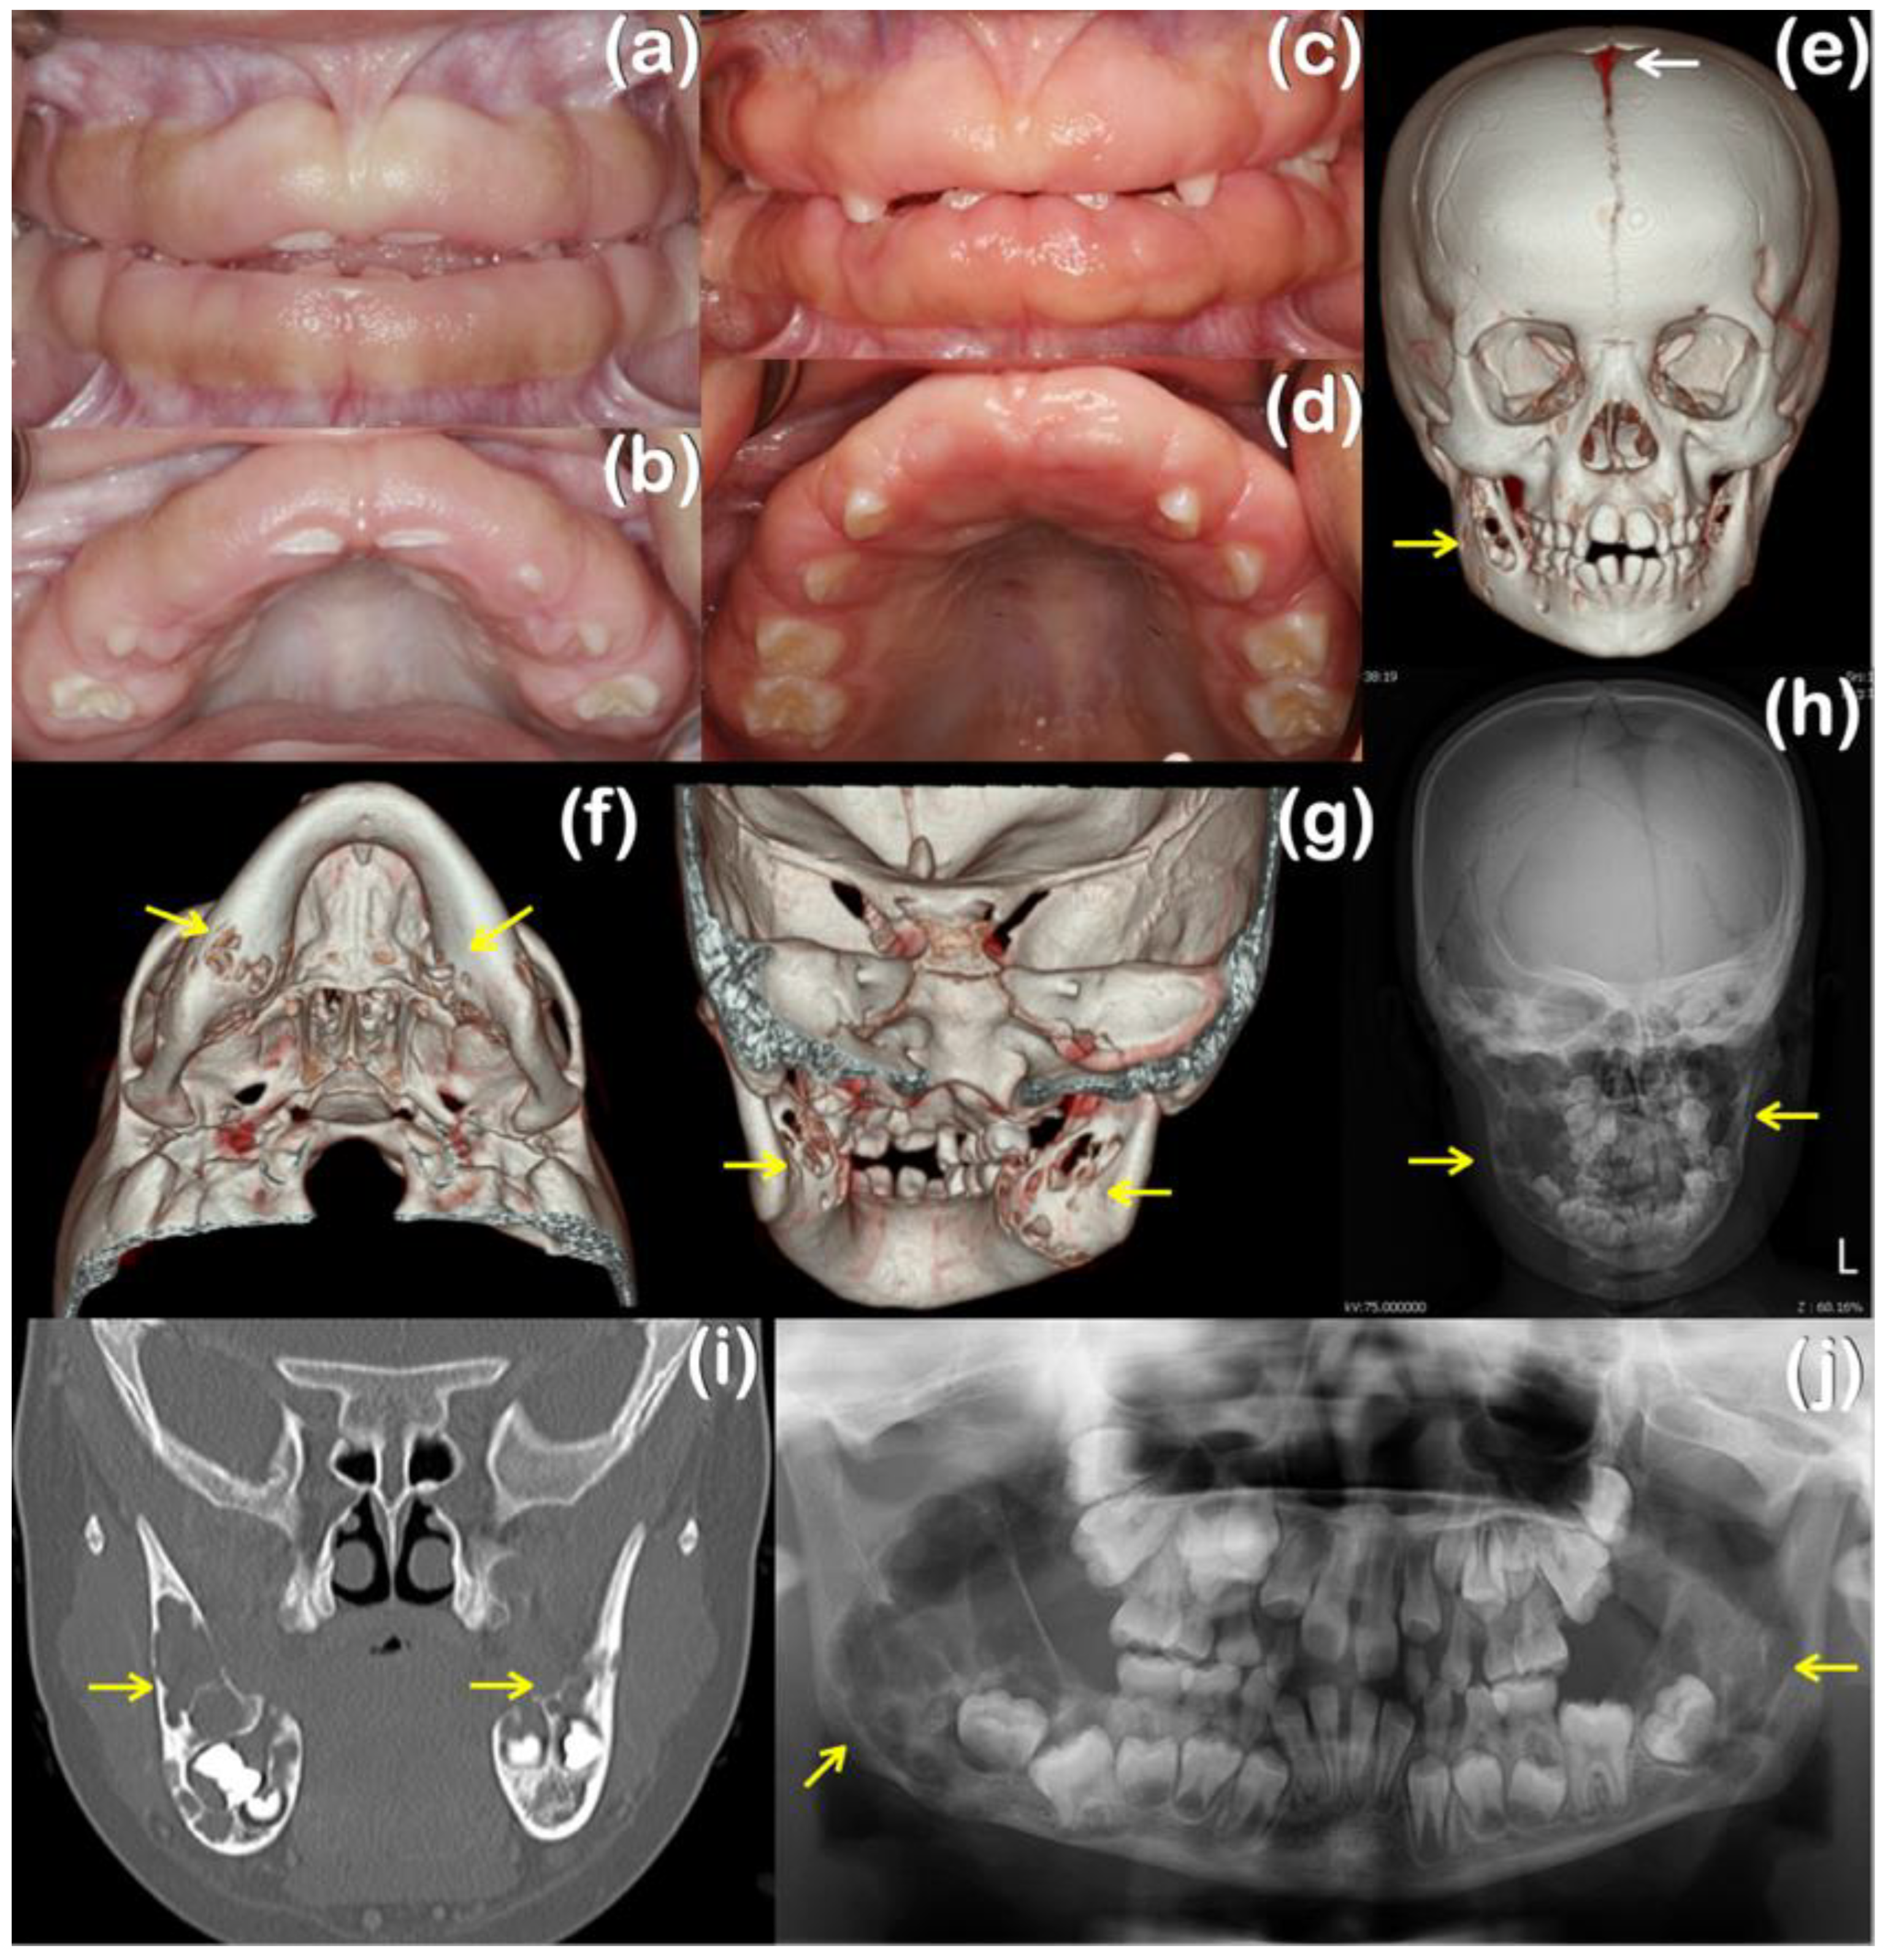

| Families | Patients | Phenotypes | Clinical Findings | Variants | Prediction/Ranking |

|---|---|---|---|---|---|

| 1 | 1 (Female) | Ramon Syndrome | Gingival fibromatosis, cherubism-like lesions, a persistent open anterior fontanelle, focal epilepsy, left eye amblyopia | TBC1D2B variant NM_144572.2; NP_653173.1 c.1879_1880del p.Glu627LysfsTer61 chr 15-78305554-TTC-T Novel | MutationTaster: Disease causing Prob = 1 PolyPhen-2: N/A SIFT: Damaging; score = 0.858 CADD: N/A DANN: N/A Varsome: N/A |

| 2 | 2 (Male) | Hereditary gingival fibromatosis | Gingival fibromatosis | TBC1D2B variant NM_144572.2; NP_653173.1 c.2471A>G p.Tyr824Cys chr 15-78295750-T-C rs199928887 MAF = 0.00001301 KREMEN2 variant NM_172229.3; NP_757384.1 c.892C>T p.Arg298Cys chr 16-3017162-C-T Novel | MutationTaster: Disease causing Prob = 0.999153978449563 PolyPhen-2: Probably damaging; score = 0.999 SIFT: Damaging; score = 0.01 CADD score = 22.8 DANN score = 0.9935 Varsome: Uncertain Significance MutationTaster: Disease causing Prob = 0.876965507429932 PolyPhen-2: Probably damaging; score = 0.994 SIFT: Tolerated; score = 0.18 CADD score = 23.5 1 DANN score = 0.9981 2 Varsome: Uncertain significance |

| 3 (Male) | Hereditary gingival fibromatosis | Gingival fibromatosis, epithelial dysplasia, dense mandibular bone | |||

| 4 (Male) | Hereditary gingival fibromatosis | Gingival fibromatosis, dense mandibular bone |